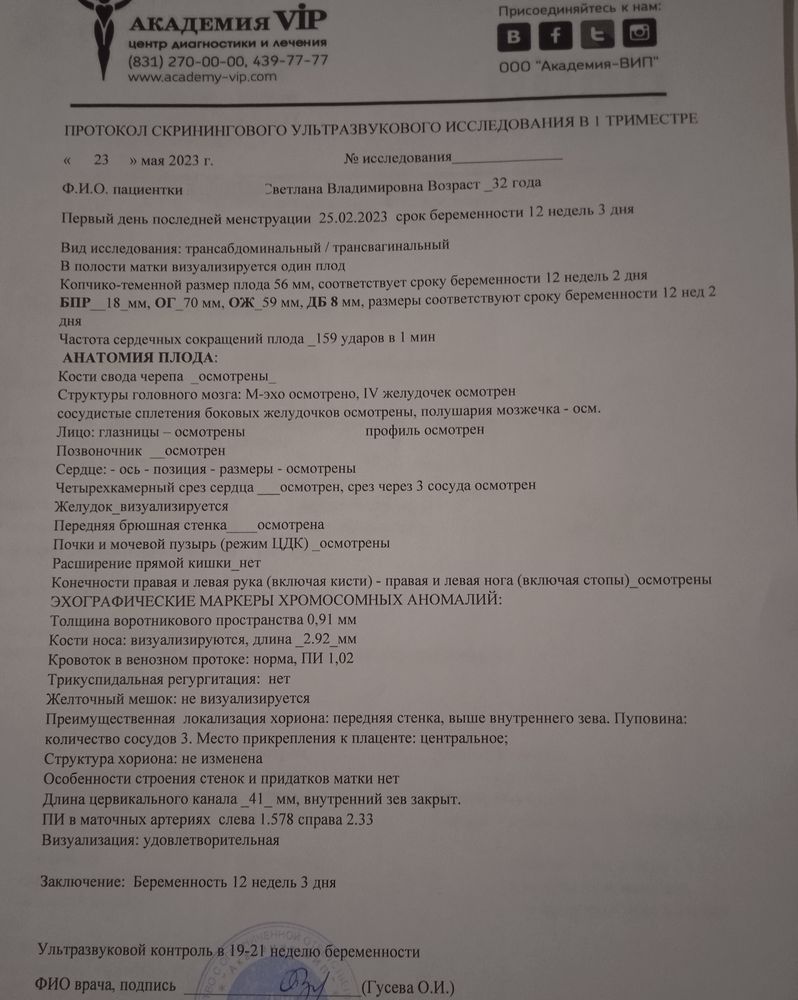

К этому врачу на это время уже пришли пациенты... Начали разбираться а меня записали не на 23 мая а на 23 июня🥴Муж после операции на колено, рулил такое расстояние, я думала нас отправят ни с чем.. Но предложили осмотр у другого врача, кмн,стаж 36 лет, я конечно расстроилась но согласилась. Василёк наш тоже видимо был не настроен показывать себя как надо и как бы мы не старались, что бы мы не делали, в профиль он не лёг, кувыркался швырялся но в профиль нет, в итоге кость носа осматривали с лица, складку(твп) вообще не знаю с какой стороны, зато торчок показал во всей красе 🙈врач сказала если не отпадёт мальчик будет 🤞🙌тут конечно я расплылась.... Появилась надежда что наша мечта о сынуле всё таки осуществится🙏Я с 9 утра до сдачи крови в 5 вечера была голодная(ещё и с ночной смены на ногах не спамши🤪),кровь сдала, попросила горячего чая, пока ждали заключения, всё хорошо, риски низкие, фото в этот раз мы красивые не получили, Василёк и там не поддался🤪А сегодня в городе я прошла скрининг по омс, на УЗИ меня опять крутили вертели, ну не хочет дитя что бы его разглядывали, вроде тоже всё хорошо, правда кровь недели через 2 с рисками, но я уже особо не жду, но пусть будет. Врач в конце, пол могу сказать если хочешь узнать, я говорю там торчок☺она говорит да, там мальчик 🙏Я пока сильно не обольщаюсь, но очень хочу что бы у нас и не отпало и не рассосалось ничего и моё материнское сердце немного залечит наш маленький сынок о котором мы с папой так мечтаем🙏🙏🙏но главное что бы живыми здоровыми и в срок 🙏💫

Ксю, вот результат в жц и пометки врача что в норме а что нет🙂кровь норма

Ксю, вот результат в жц и пометки врача что в норме а что нет🙂кровь норма